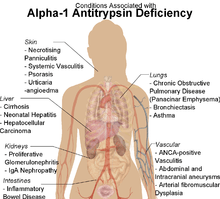

Alpha 1-antitrypsin deficiency (α1-antitrypsin deficiency, A1AD) is a genetic disorder that causes defective production of alpha 1-antitrypsin (A1AT), leading to decreased A1AT activity in the blood and lungs, and deposition of excessive abnormal A1AT protein in liver cells.[1][2] There are several forms and degrees of deficiency; the form and degree depend on whether the sufferer has one or two copies of a defective allele. In the literature it has been described as either a recessive or co-dominant trait as there is some evidence that smoking heterozygotes are affected.[3] Severe A1AT deficiency causes panacinar emphysema or COPD in adult life in many people with the condition (especially if they are exposed to cigarette smoke).[4] The disorder can lead to various liver diseases in a minority of children and adults, and occasionally more unusual problems.[4] It is treated through avoidance of damaging inhalants and, in severe cases, by intravenous infusions of the A1AT protein or by transplantation of the liver or lungs. It usually produces some degree of disability and reduces life expectancy.[1]

Symptoms of alpha-1 antitrypsin deficiency include shortness of breath, wheezing, rhonchi, and rales. The patient's symptoms may resemble recurrent respiratory infections or asthma that does not respond to treatment. Individuals with A1AD may develop emphysema during their thirties or forties even without a history of significant smoking, though smoking greatly increases the risk for emphysema.[1] A1AD causes impaired liver function in some patients and may lead to cirrhosis and liver failure (15%). In newborns, alpha-1 antitrypsin deficiency has indicators that include early onset jaundice followed by prolonged jaundice. It is a leading indication for liver transplantation in newborns.

α1-antitrypsin deficiency has been associated with a number of diseases:

- Cirrhosis

- COPD

- Pneumothorax

- Asthma

- Granulomatosis with polyangiitis

- Pancreatitis

- Gallstones

- Bronchiectasis

- Pelvic organ prolapse[5]

- Primary sclerosing cholangitis

- Autoimmune hepatitis

- Emphysema, predominantly involving the lower lobes and causing bullae

- Secondary Membranoproliferative Glomerulonephritis

- Cancer